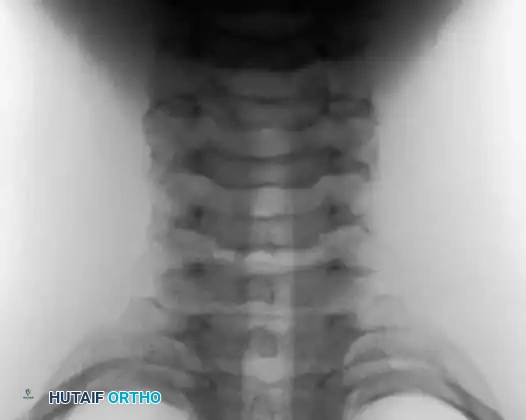

Anteroposterior and lateral radiographs of the cervical spine in a 10-year-old boy presenting with a 1-month history of severe neck pain, demonstrating a distinct lesion of the C3 spinous process.